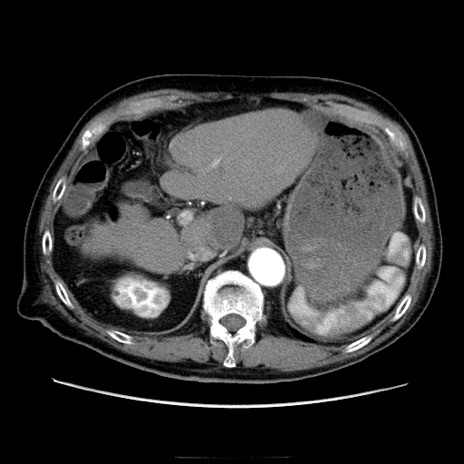

冠状断像

【症例】70歳代男性

【現病歴】肝硬変・肝細胞癌にてかかりつけの方。約9時間前に食後より腹痛出現。症状が徐々に増悪し、嘔吐出現したため来院。

【既往歴】肝硬変、肝細胞癌(RFA、TACE後)